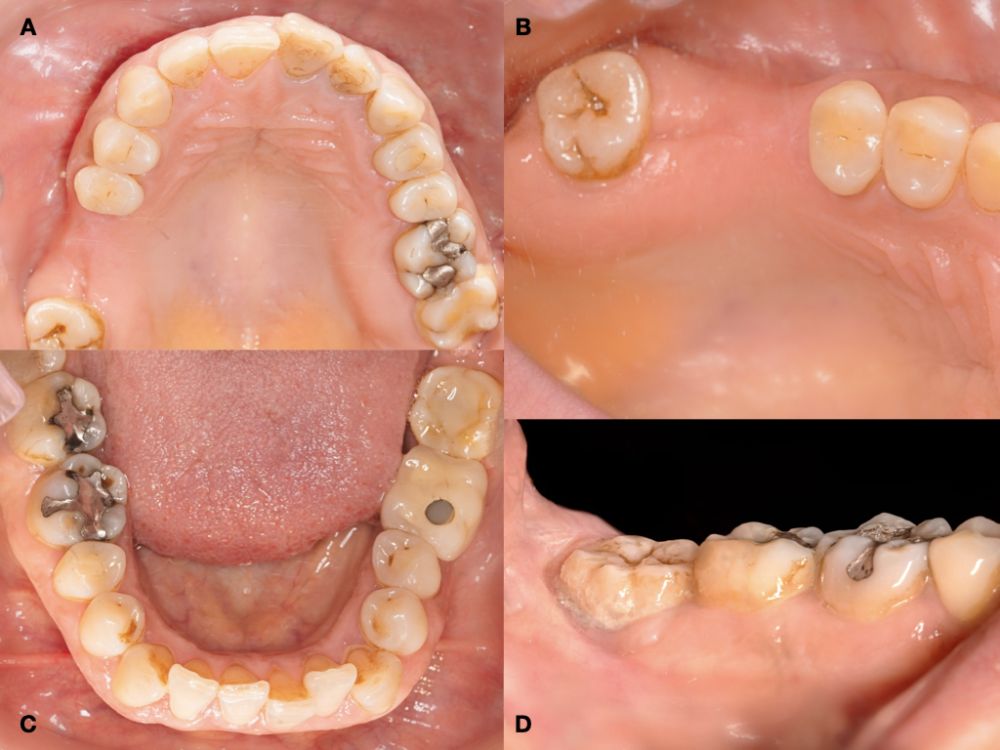

En la historia clínica, no se evidenciaron antecedentes médico-quirúrgicos de interés, alergias medicamentosas conocidas ni hábitos nocivos. A la exploración intraoral, se apreciaron las ausencias de 1.6 y 1.7 y la presencia del 1.8 y 4.8 (Figura 1). En la exploración radiográfica mediante escáner de haz cónico (CBCT) se apreció una altura residual de 5,0 mm en 1.6, donde se podría colocar un implante simultáneo, y de 2,6 mm en la zona del 1.7, dificultando la colocación de un implante de manera simultánea a la elevación de seno de acceso lateral (Figura 2).